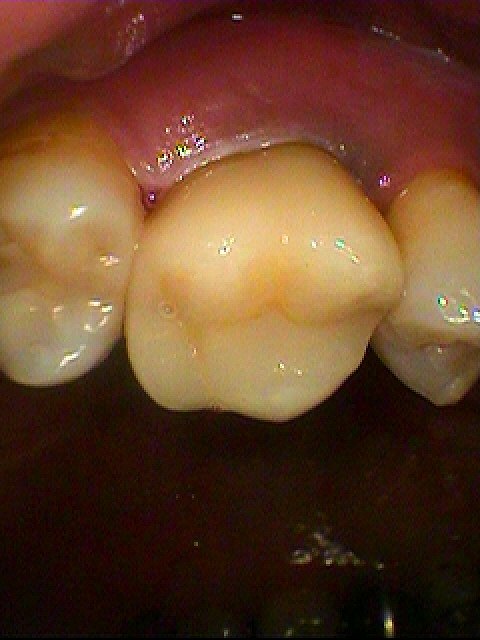

セレックオールセラミッククラウンが入りました

このように綺麗に修復しています